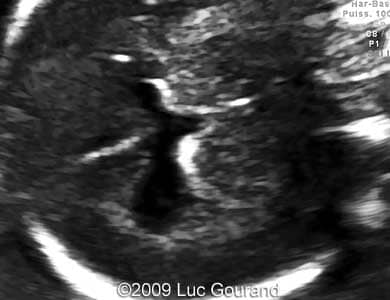

Images 1,2: Image 1 shows an axial plane of the brain, thalami are well separated, cavum septi pellucidi is not seen. Image 2 shows the confluence of the posterior horns of the lateral ventricles.

Case262_1

Case262_2

Images 3,4: Image 3 shows the confluence of the posterior horns of the lateral ventricles. Image 4 shows the absence of corpus callosum, the arrows indicate a wavy hypoechogenic structure in the mid-line, which could be detected on the MRI as well (see Image 7).

Case262_6

Case262_5